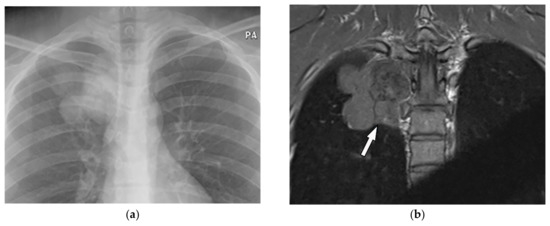

Figure 5.

A 35-year-old man with chronic vague chest pain. (a) Frontal chest radiograph shows a right-sided lobulated mass with a cervicothoracic sign indicating the retro mediastinal location of the lesions. (b) Coronal T1W image shows lobulated paraspinal mass isointense to muscle (arrow). (c) Axial T2W fat-saturated image demonstrates heterogeneous high signal intensity with lobulated margin and internal foci of low signal intensity representing calcifications seen on CT (not shown). There is no neural foraminal extension.